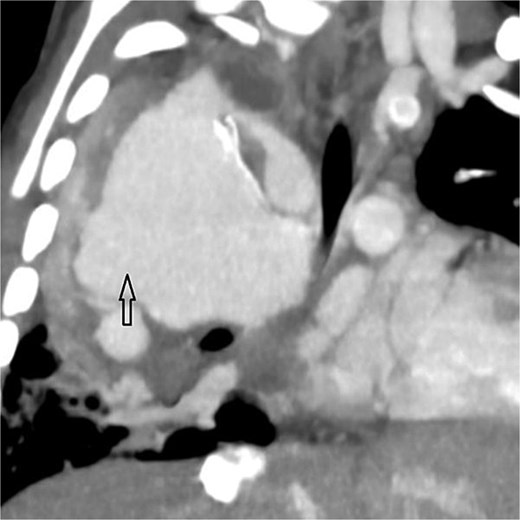

Coronal oblique maximum-intensity-projection reconstruction of thoracic CT angiography showing a large thrombosed pseudoaneurysm of the right subclavian artery at the anastomosis with the modified Blalock–Taussig–Thomas shunt, causing significant mediastinal mass effect.

Urgent transthoracic echocardiography demonstrated a large echodense mass in the right hemithorax, compression of the right atrium and reduced flow through the right-sided shunt. Computed tomography angiography (CTA) confirmed a massive saccular pseudoaneurysm (≈8 × 7 × 6 cm) arising from the anastomosis between the right subclavian artery and the mBTTS graft, completely thrombosed without active contrast extravasation (Fig. 1). There was complete thrombotic occlusion of the right pulmonary artery, right lung collapse due to extrinsic compression and right lower-lobe consolidation consistent with pneumonia (Fig. 2). CTA also revealed left isomerism with central liver and polysplenism (Fig. 3) and a horseshoe kidney (Fig. 4), suggesting a previously unrecognized polymalformative syndrome.